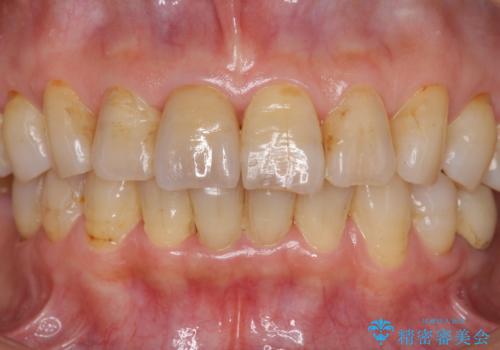

天然歯を模した ハイグレードオールセラミッククラウン

当法人でご提案できる最上位クラスのジルコニアクラウンです。

透明感や周囲の歯との色の調和に大変ご満足いただけました。